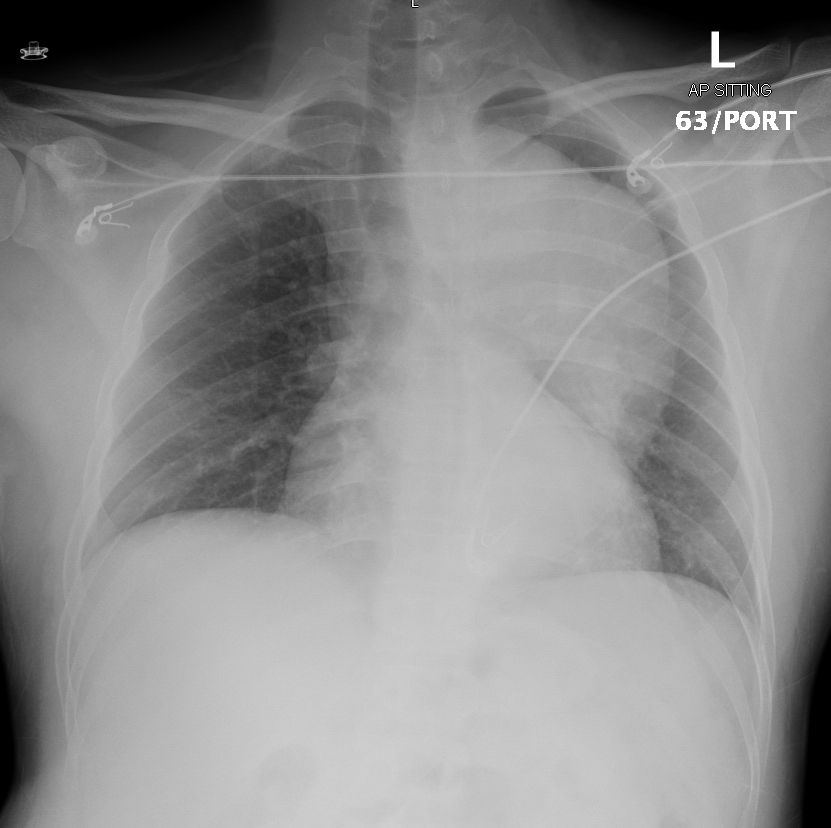

55 male chronic HTN not on optimum medical Treatment, after a fight with his colleagues developed Right Side Hemiparesis.  Diagnosis ?  What further i